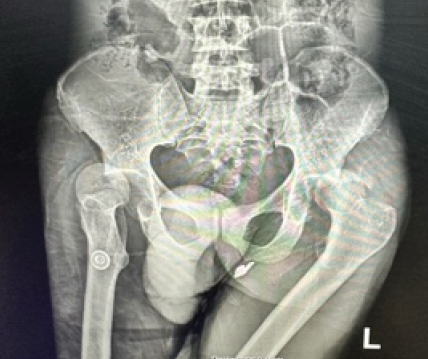

Asymmetrical Bilateral Complex Dislocations of the Hips: A Rare Case Report

Papa Kwabena Offeh Kyei , Tamsanqa Joseph Mazibuko , Collen Sandile Nkosi

………………………………p.250-254